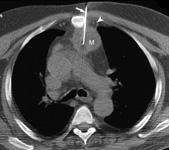

The development of computed tomography (CT), ultrasound and magnetic resonance imaging (MRI), allowed physicians to use advanced imaging guidance with biopsies. Imaging-guided percutaneous needle biopsies achieve greater precision in targeting lesions, resulting in high sensitivities and low complication rates.

For the study, researchers looked for biopsy trends in Medicare claims data from 1997 through 2008 for 10 anatomical regions. Biopsy procedures increased from 1,380 per 100,000 Medicare enrollees in 1997 to 1,945 biopsies in 2008, representing a compound annual growth rate of 3 percent. In 2008, 67 percent of all biopsies were performed percutaneously, compared to 59 percent in 1997.

The increased percentage of imaging-guided percutaneous biopsies corresponded to decreases in the percentages of the more invasive open biopsies and non-imaging-guided percutaneous biopsies.